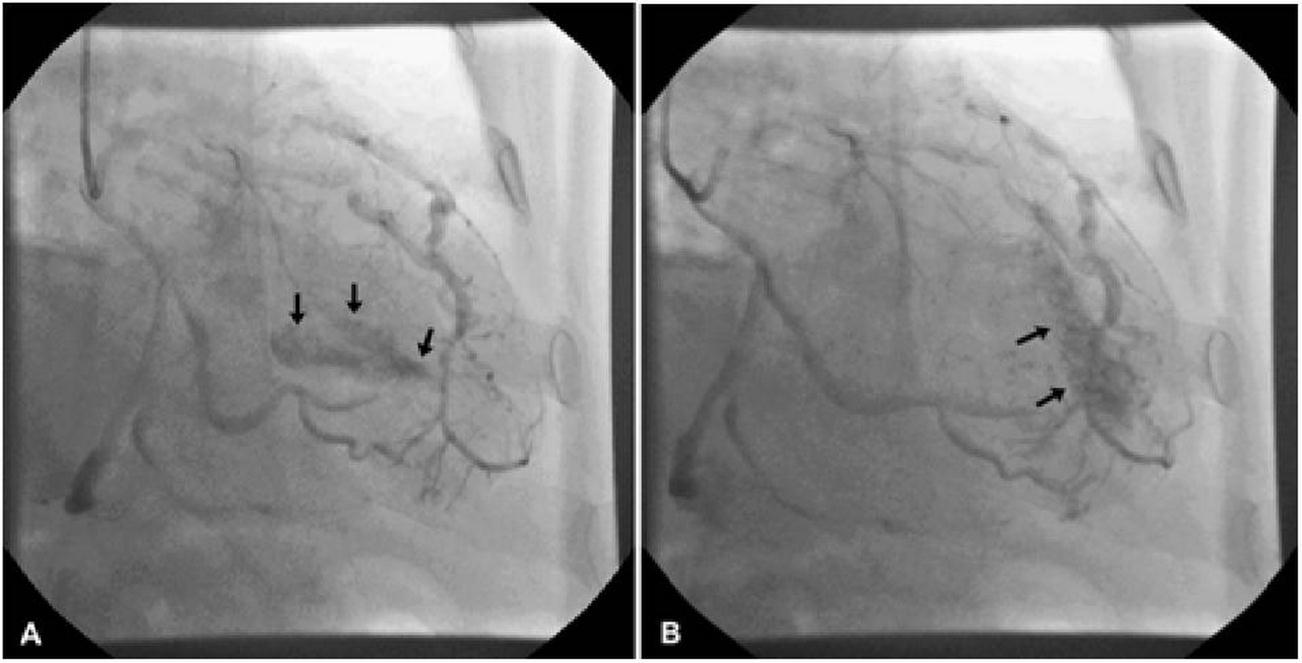

A 62 years old man six years ago underwent coronary angiography due to atypical chest pain. No coronary stenosis was observed while multiple coronary fistula coming from middle tract of left anterior descending (LAD) artery and draining to left ventricle cavity were detected (Figure 1). At discharged, he undertook antiaggregant therapy and no fistula’s closure indication was advised.

Figure 1.A/B. Left anterior descending artery fistula in left ventricular cavity: an angiography perspective.